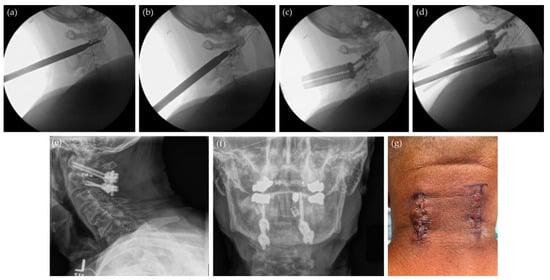

7.1. Minimally Invasive Posterior Cervical Decompression and Fusion

7.2. Endoscopic Odontoidectomy and Atlantoaxial Fusion